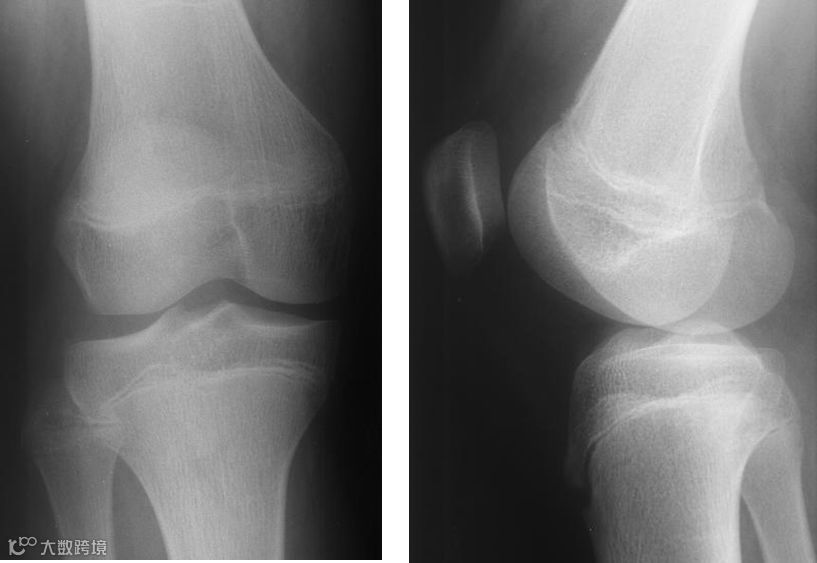

2、髌骨骨折

功能锻炼方法:

后早期疼痛稍减轻后,病人即可开始练习股四头肌静止收缩,髋、膝、踝、趾关节主动运动。

固定后3~5天可两腿直腿抬高和膝关节屈伸运动,扶拐进行患肢负重练习。

石膏固定的病人,4~8周可去除石膏,此时可做髌骨倾向被动活动,做主动屈膝活动练习,6~8周可负重行走。